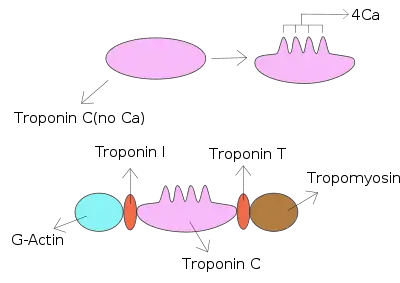

The troponin complex is responsible for coupling the sarcomere contraction cycle to variations in intracellular calcium concentration. Increased troponin T levels after an episode of chest pain indicates myocardial infarction.[7] It was discovered by the German physician Hugo A. Katus at the University of Heidelberg. He also developed the troponin T assay.[8] In patients with stable coronary artery disease, the troponin T concentration has long been found to be significantly associated with the incidence of cardiovascular death and heart failure, but it was 2014 before it began to be accepted as a predictor of who would later suffer acute myocardial infarction (heart attack).[9][10]